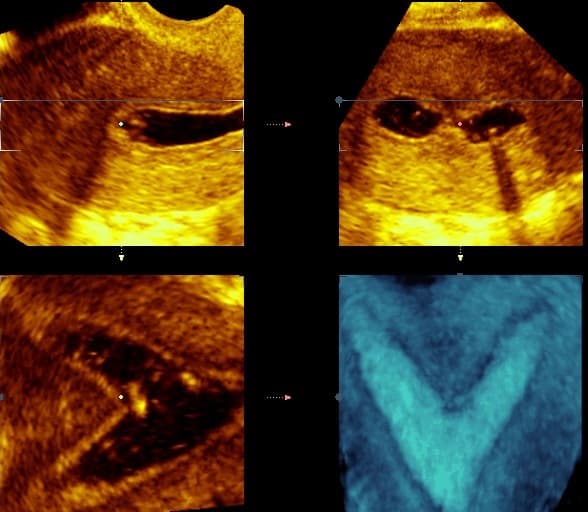

Ultrazvučna procjena maternične šupljine danas je najjednostavniji i najpristupačniji oblik postavljanja sumnje i često dijagnoze razvojnih anomalija. Konačna dijagnoza uz planiranje korekcije u žena koje žele ostvariti trudnoću postavlja se histeroskopskim i laparoskopskim putem kada se procjenjuje i opsežnost anomalije odnosno prisutnost i prohodnost jajovoda.

Transvaginalnim ultrazvukom je osjetljivost u dijagnostici septiranog uterusa 100%, a specifičnost 80%. Transvaginalnim ultrazvukom može se precizno odrediti indentacija (uleknuće) u fundusu i na taj način točno razvrstati radi li se o septumu koji treba operirati (aplaniran fundus) ili dvorogoj maternici, koju ne treba operirati (konveksan fundus).

Diferencijalnu dijagnostiku osobito pospješuje primjena trodimenzionalnog i kontrastnog ultrazvuka, kada se u materište instilira fiziološka otopina ili kontrast koja se potom pregledava u svim dimenzijama. Kontrastni ultrazvuk ne samo da je koristan u evaluaciji kongenitalnih anomalija uterusa, već omogućuje i ispitivanje prohodnosti jajovoda. Za trodimenzionalni ultrazvuk se kaže da nalazi uterusa koreliraju s vanjskom konfiguracijom uterusa nađenom pri laparoskopiji, da mu je osjetljivost i specifičnost 100% za dijagnozu velikih anomalija Müllerovih cijevi, i 100% preciznost za bikornualni uterus.